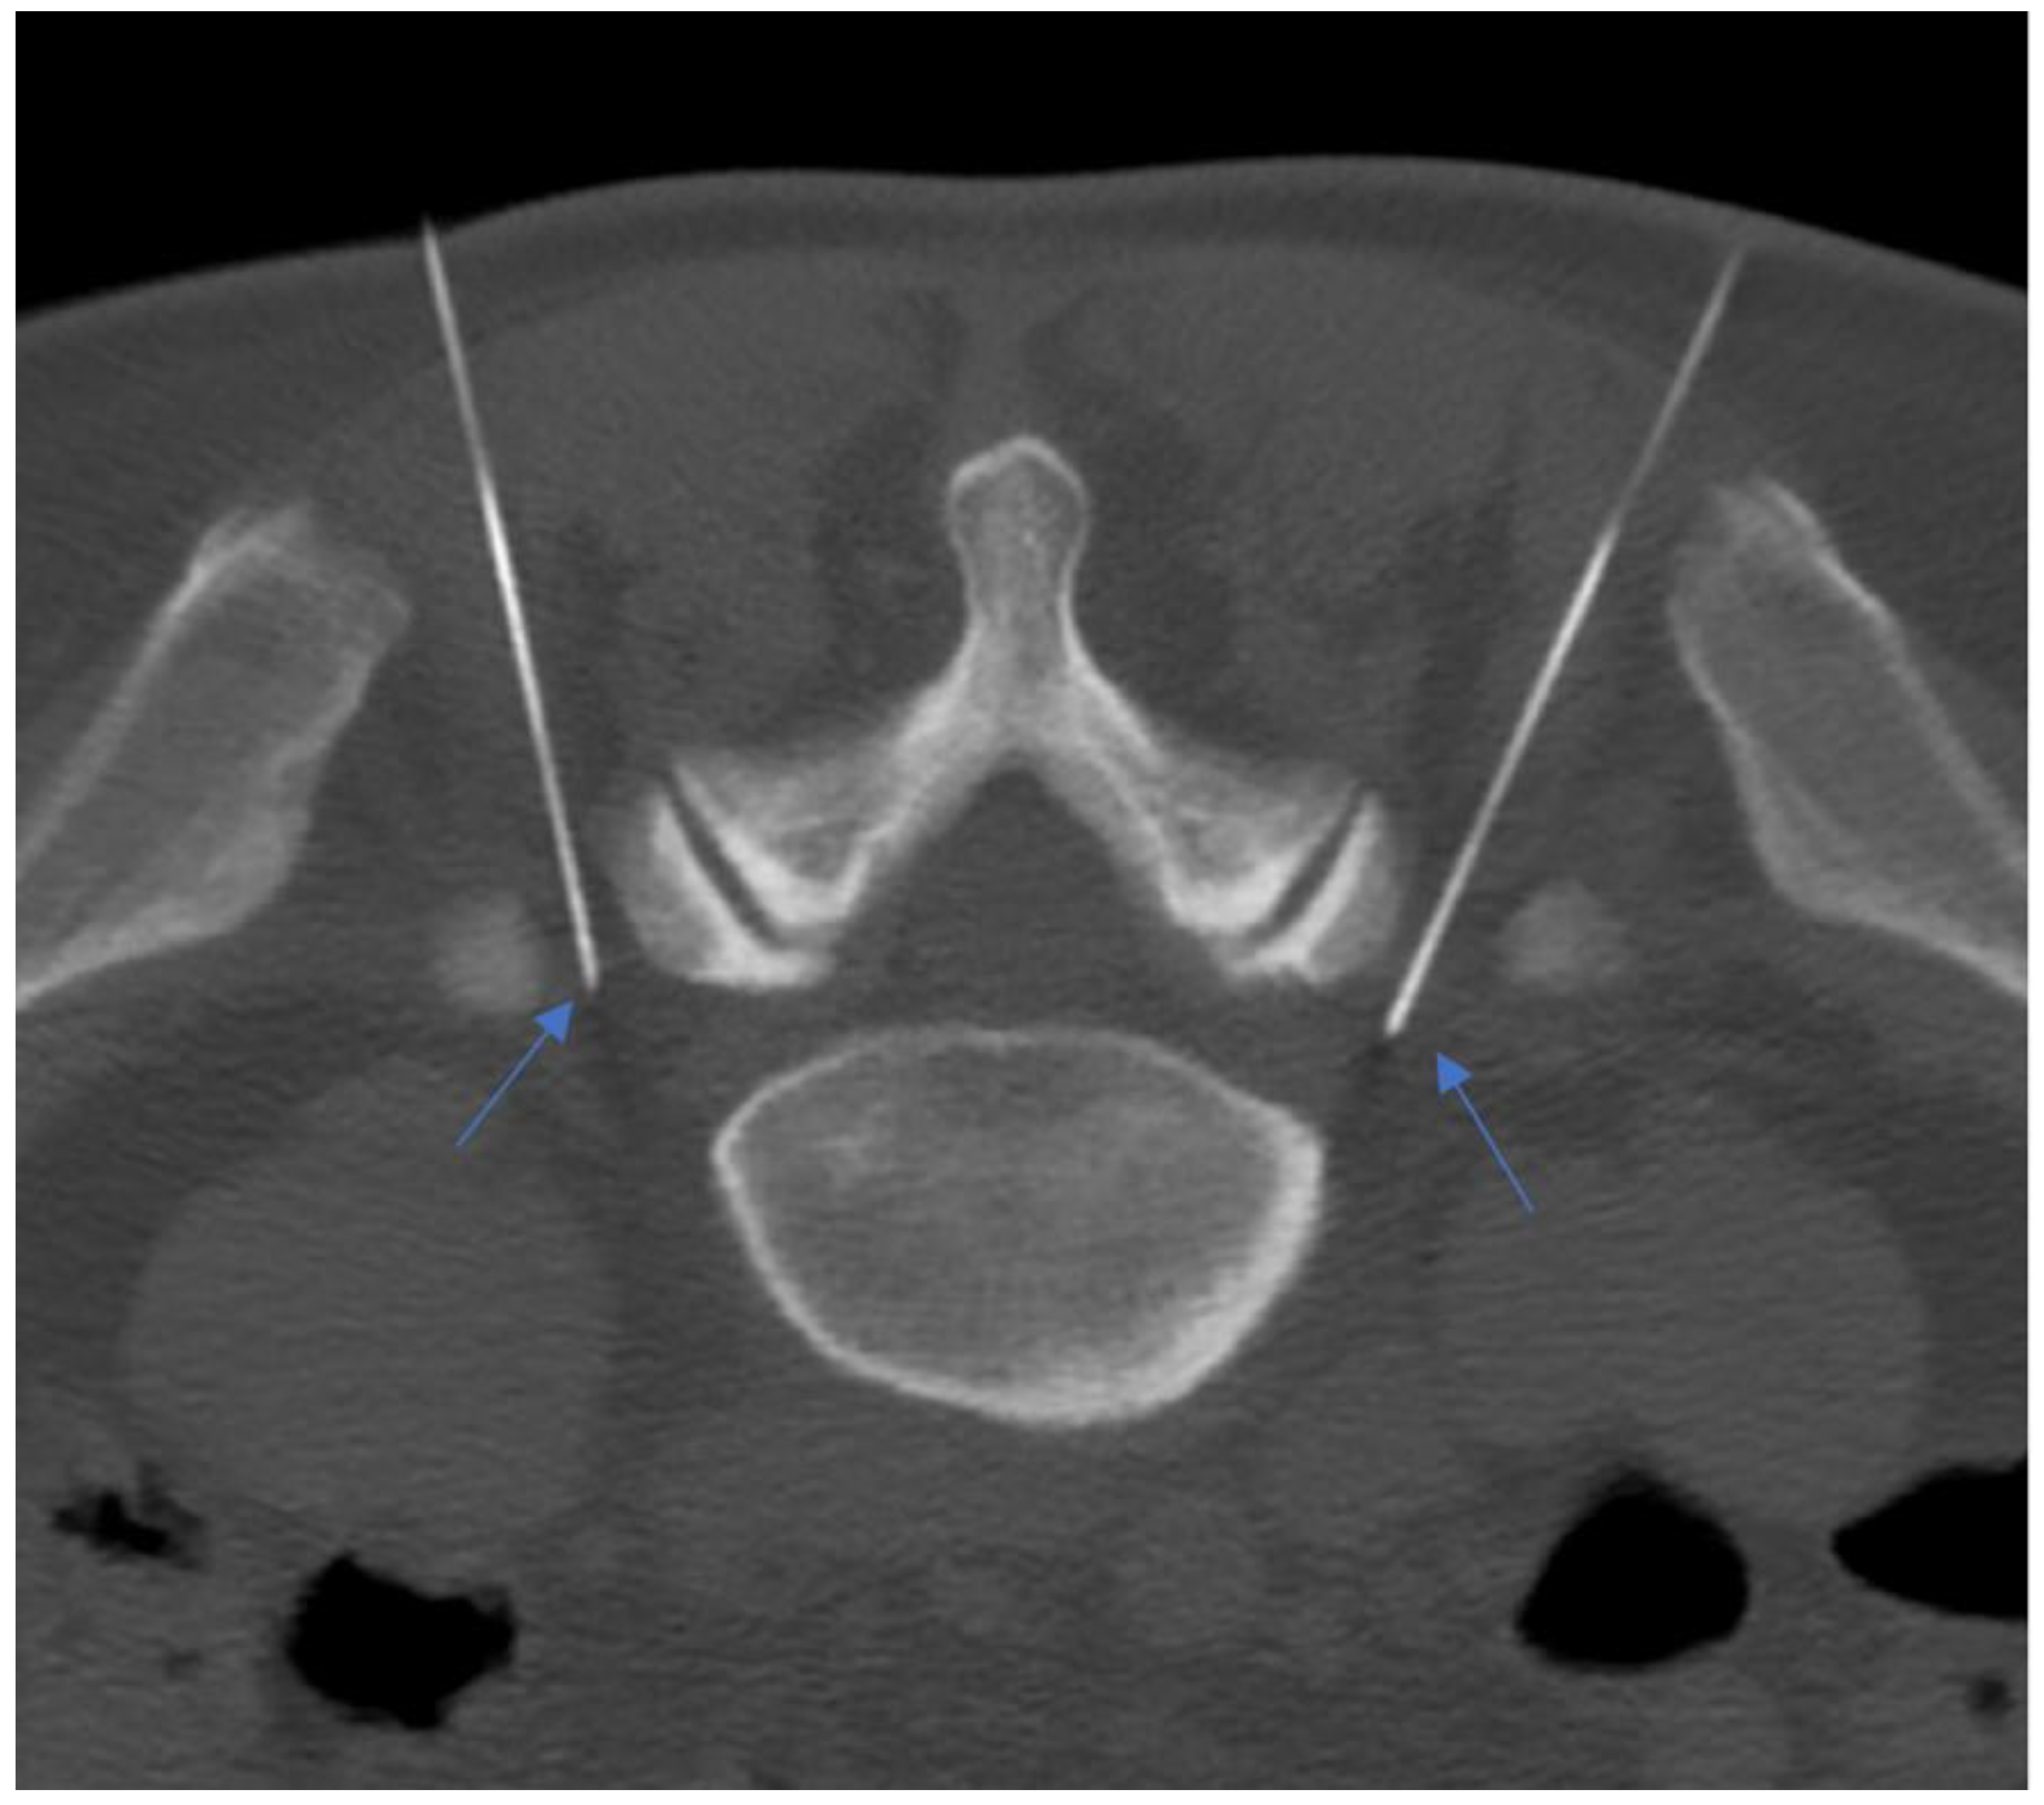

- Napoli, A.; Alfieri, G.; De Maio, A.; Panella, E.; Scipione, R.; Facchini, G.; Albisinni, U.; Spinnato, P.; Nardis, P.G.; Tramutoli, R.; et al. CT-Guided Pulsed Radiofrequency Combined with Steroid Injection for Sciatica from Herniated Disk: A Randomized Trial. Radiology 2023, 307, e221478. [Google Scholar] [CrossRef] [PubMed]